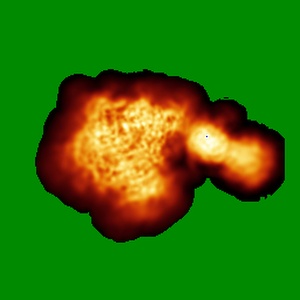

Cryo-EM map of DH898.1 Fab-dimer bound near the CD4 binding site of HIV-1 Env CH848 SOSIP trimer

Single-particle4.7 Å

Sample: Cryo-EM structure of DH898.1 Fab-dimer bound near the CD4 binding site of HIV-1 Env CH848 SOSIP trimer.